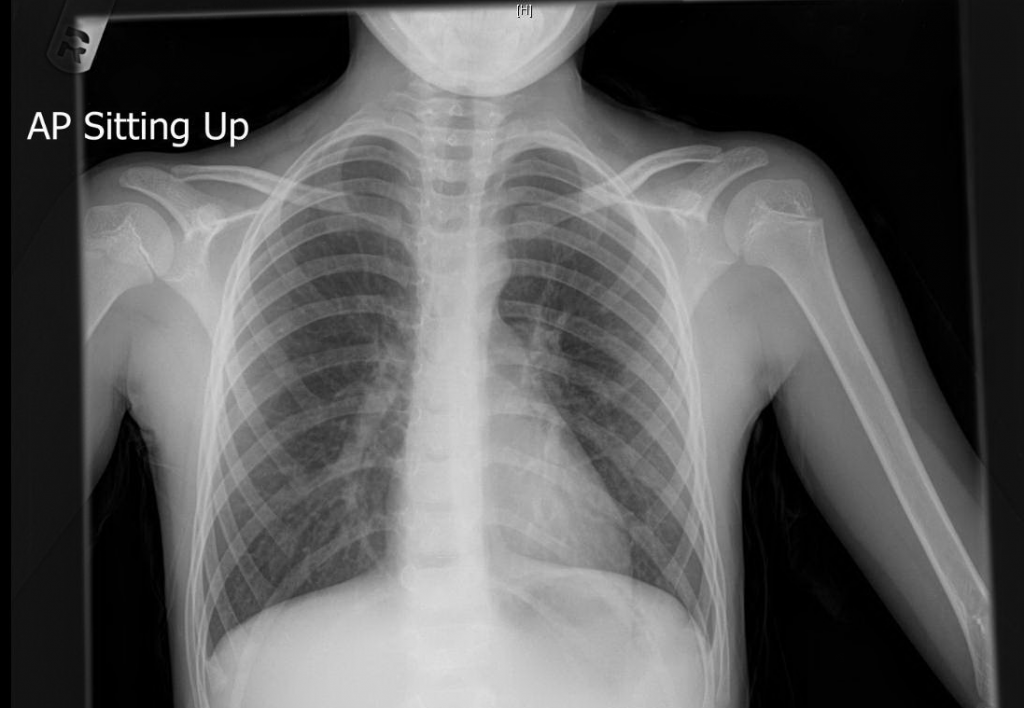

From www.criticalcare-sonography.com

Pulmonary hypertension in a child Critical Care Sonography Chest X Ray For Hypertension It may be used to check for other lung conditions that can. The reported causes were ph, congenital heart disease (overcirculation lesions such. Although findings may be nonspecific, 90% of patients with idiopathic pah (ipah) will have an abnormal chest radiograph at the time of diagnosis. Further imaging such as ct. The most common clinical presentation of pa dissection was. Chest X Ray For Hypertension.